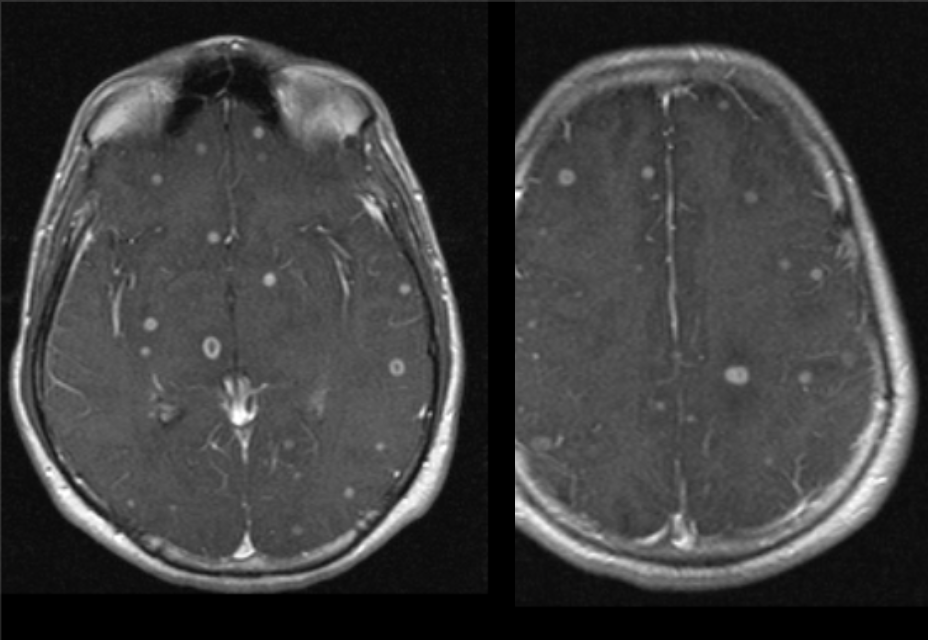

A 54 year-old man presented with headaches and weakness on his left side.

Abscess

Imaging